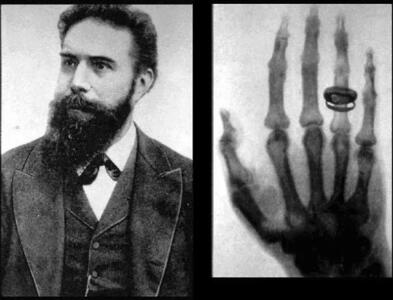

اشعه ایکس

به لطف یک کشف تصادفی، دانشمندان از یک منبع ستارهای کاملا جدید از انفجار تابش اشعه ایکس آگاه شدهاند.

اسکن اشعه ایکس به معمای چگونگی قرار گرفتن تابوت بدون دریچه لیدی چنت پاسخ میدهد.

سامسونگ به دلیل عدم رعایت استانداردها و قرار گرفتن ۲ کارمند در معرض اشعه ایکس کمتر از ۸ هزار دلار جریمه شد.

شرکت سامسونگ به دلیل عدم رعایت استانداردها ۸ هزار دلار جریمه شد.

کشف بزرگترین الماس قرن با اشعه ایکس! - تکناک

شرکت کانادایی Lucara Diamond با استفاده از فناوری انتقال اشعه ایکس، دومین الماس بزرگ جهان را در بوتسوانا کشف کرده است.

اشعه ایکس با دوز پایین میتواند سلولهای تومور مغزی را نابود کند!

پروفسور Pu Kanyi نویسنده ارشد و همکار این مطالعه گفت: «ما از دوزهای بسیار پایین اشعه ایکس و MRAPهای کشنده سرطان استفاده کردیم.